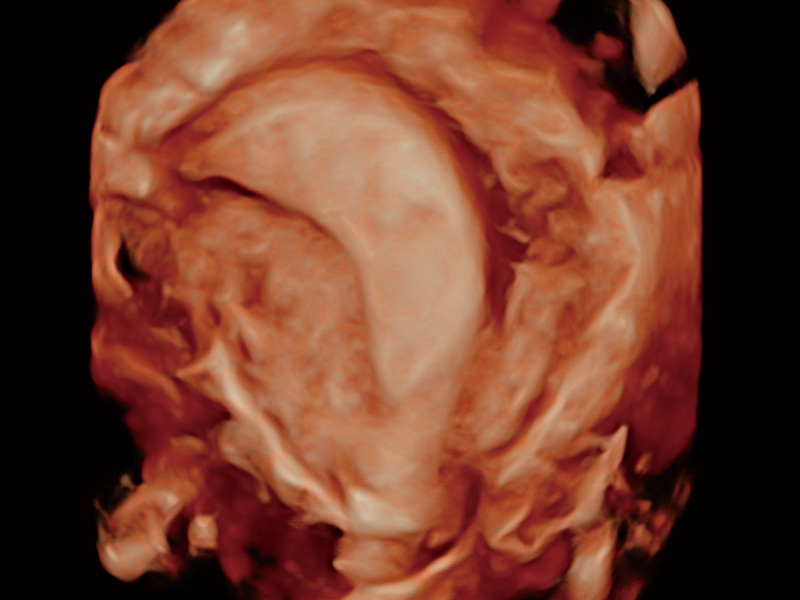

子宫内膜息肉

输卵管间质部妊娠